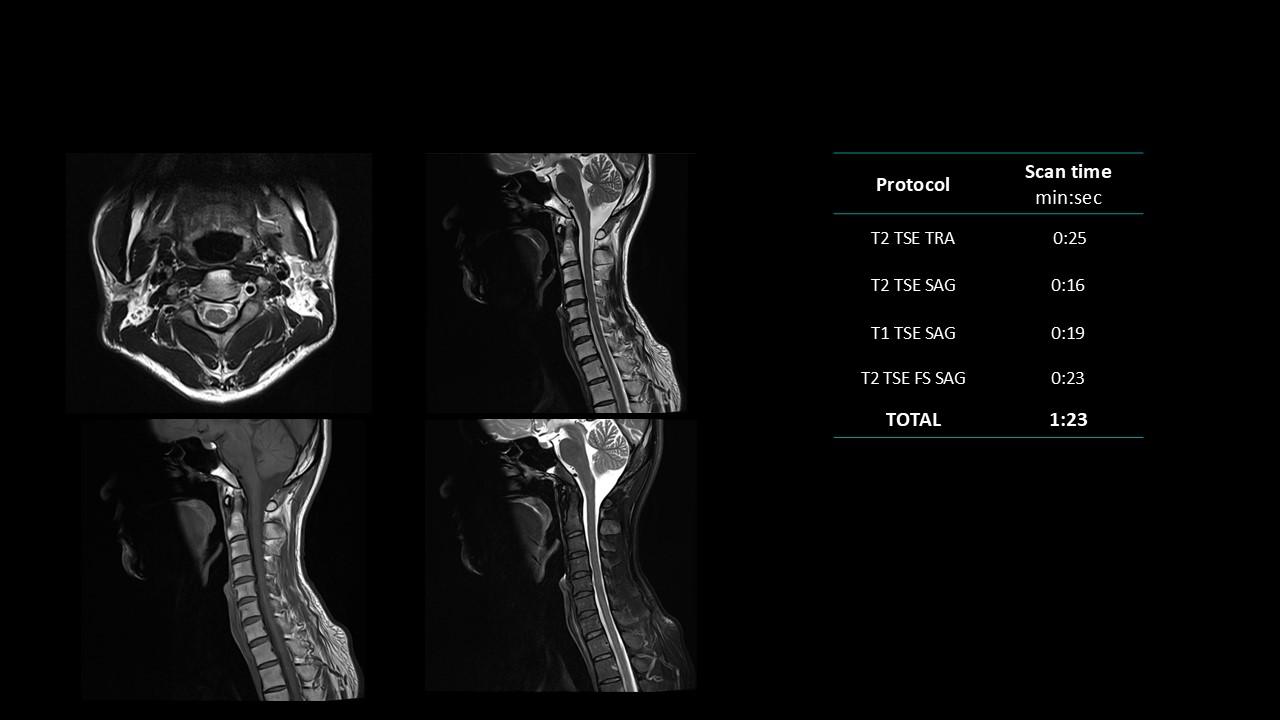

The Deep Resolve protocols are a set of advanced 3T MR imaging protocols designed to achieve high-quality diagnostic imaging with significantly reduced acquisition times.

Enabled by Deep Resolve, the AI-powered image reconstruction technology, these protocols deliver high-quality scans in approximately three minutes across a wide range of anatomical regions.

Developed and meticulously evaluated by Dr. Seong-ho Lee of Leaders Radiology Hospital in Seoul, Korea, the protocols integrate deep learning technology to enhance imaging efficiency while maintaining diagnostic detail.

By reducing scan duration, they improve workflow efficiency and patient experience without compromising image quality.